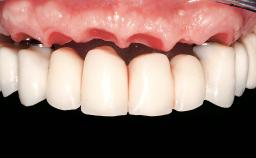

Immediate Loading of Two Implants in the Mandible and Final Restoration with a Bar-Supported RDP

A 56-year-old female patient was referred to the clinic because of retention problems with her mandibular denture. She had been completely edentulous for more than 33 years and wore her sixth set of complete conventional dentures, which had been delivered 5 years previously. An oral surgeon had performed a vestibuloplasty in the interforaminal region of the mandible with a piece of skin tissue 12 years earlier. The panoramic radiograph and lateral cephalometric radiograph exhibited the hypotrophy of the inferior alveolar process. The mandible was a Cawood class VI,and the height of the mandible in the interforaminal zone was 15 mm.